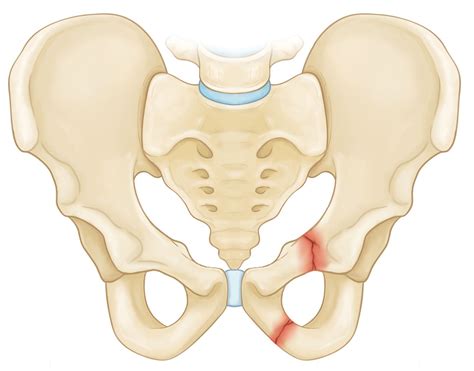

Fractures

Fractures of the inferior pubic ramus are relatively common, often occurring as a result of high-impact trauma, such as motor vehicle accidents or falls from significant heights. These fractures can be isolated or part of a more complex pelvic injury. Symptoms may include:

• Severe pain in the pelvic region

• Difficulty walking or standing

• Swelling and bruising

Treatment for inferior pubic ramus fractures typically involves immobilization and rest, followed by physical therapy to regain strength and mobility. In severe cases, surgical intervention may be necessary to stabilize the fracture.